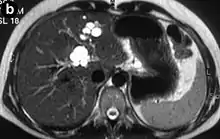

Turbo spin echo T2-weighted axial MRI of Caroli disease, showing cystic dilatations of bile ducts (shown as white).[1]

Modern imaging techniques allow the diagnosis to be made more easily and without invasive imaging of the biliary tree.[9] Commonly, the disease is limited to the left lobe of the liver. Images taken by CT scan, X-ray, or MRI show enlarged intrahepatic (in the liver) bile ducts due to ectasia. Using an ultrasound, tubular dilation of the bile ducts can be seen. On a CT scan, Caroli disease can be observed by noting the many fluid-filled, tubular structures extending to the liver.[4] A high-contrast CT must be used to distinguish the difference between stones and widened ducts. Bowel gas and digestive habits make it difficult to obtain a clear sonogram, so a CT scan is a good substitution. When the intrahepatic bile duct wall has protrusions, it is clearly seen as central dots or a linear streak.[10] Caroli disease is commonly diagnosed after this “central dot sign” is detected on a CT scan or ultrasound.[10] However, cholangiography is the best, and final, approach to show the enlarged bile ducts as a result of Caroli disease.